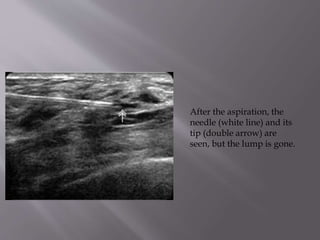

After the aspiration, the

needle (white line) and its

tip (double arrow) are

seen, but the lump is gone.

After the aspiration,the needle (white line) and its tip (double arrow) are seen, but the lump is gone.